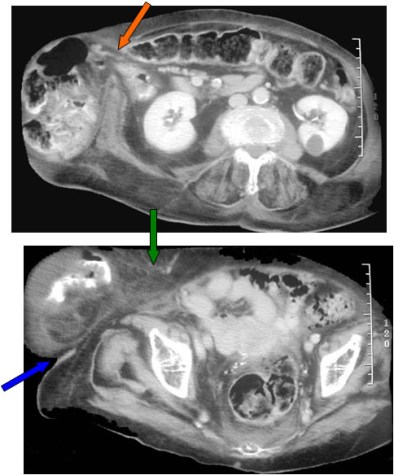

Una masa situada en la pared abdominal, como por ejemplo una hernia, se caracteriza por presentar bordes incompletos, debido a que, en algún punto de su contorno, éste se confunde con los tejidos blandos adyacentes.

El ejemplo que mostramos corresponde a una hernia, de la que sólo es visible el margen inferior (flechas).

TC de abdomen con contraste oral e iv. del mismo paciente. La imagen superior muestra la herniación de asas intestinales (flecha naranja). La imagen inferior, correspondiente a un corte de pelvis, justifica el signo: un extremo del saco herniario forma un ángulo agudo con la pared abdominal (flecha azul) y es el borde visible en la radiografía; el otro extremo se continúa con la pared abdominal (flecha verde), lo que justifica la zona incompleta de la pared de la masa.